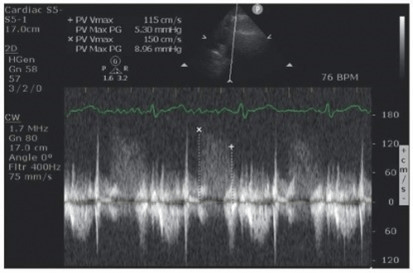

When viewing the spectral Doppler, a waveform is visible but the entire area around it is filled with white specs. What is this called?

Grayscale noise